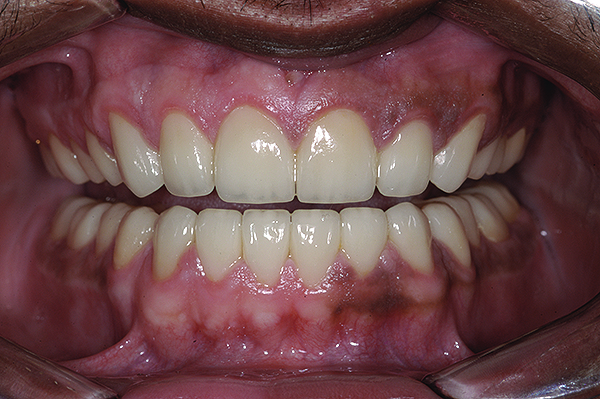

Figure 19. Postoperative frontal smile.

Figure 19

Figure 20. Postoperative 1:2 retracted frontal view.

Figure 20

The final restorations depicted restoration of form, function, and beauty, with good harmony of restoration and the periodontium (Figure 19 through Figure 25). MIP was in harmony with CR, and right and left lateral excursion discluded all posteriors with anterior group function. The postoperative orthopantomogram (OPG) (Figure 26) shows the treatment done while maintaining the vitality of anterior teeth.